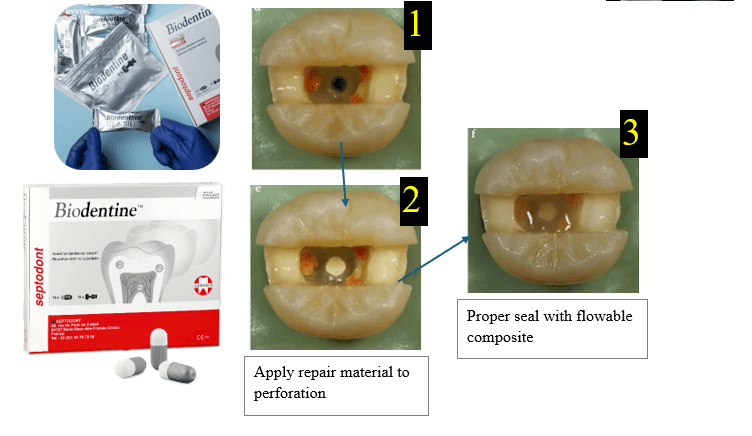

- Use premeasured MTA powder (e.g., ProRoot MTA, MTA Plus).

- Mix with sterile distilled water or the provided liquid:

- Ratio: 3:1 powder to liquid

- Consistency: moist putty (non-gritty, cohesive ball)

- Mix on glass slab or mixing pad with a stainless spatula

- If using premixed bio-ceramic putty (e.g., EndoSequence BC RRM), skip mixing (it is much easier).

- Dry the perforation site with a sterile paper point.

- But do not over-dry — MTA needs slight moisture.

- Insert MTA using:

- Map system (micro apical placement).

- Carrier gun.

- Amalgam carrier + fine condenser.

- Place small increments (1–2 mm).

- Gently condense with a plugger or micro-condenser.

- Ensure that:

- There are no voids.

- The material is flush with the chamber wall or furcation floor.

- No extrusion occurs into the sulcus or periodontium

- Place a moist cotton pellet directly over the MTA.

- Seal the access with a temporary filling.

- Let MTA set for at least 24 hours (setting time = 2 hours minimum, ideally overnight for strength).

- Apply MTA then apply temporary filling over it.

- After 24 hours apply glass ionomer, composite restoration, and make a crown.

- Some modern MTA formulas set faster (set in 15–30 minutes)

- For example:

- MTA Repair HP.

- MTA Angelus Fast Set.

- There is Biodentine, which is better and fast setting.

Step 4: Prepare MTA

Step 5: put MTA into the perforation

Step 6: Provide Moisture for Setting

Important sequence

Apply MTA, cover it with a temporary restoration, wait for proper setting, then complete the definitive coronal restoration.